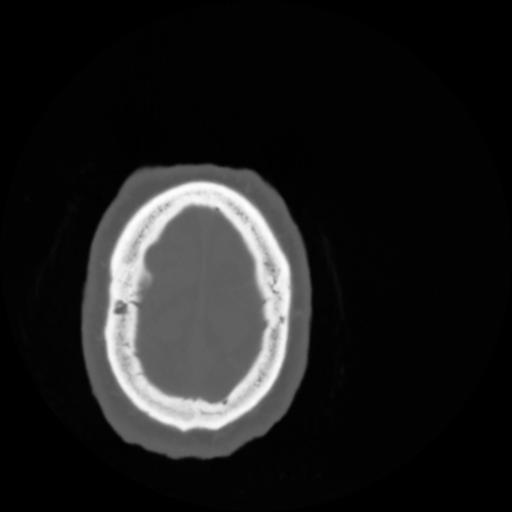

4 CEREBRO,,Vol,0.5,CEREBRO,,